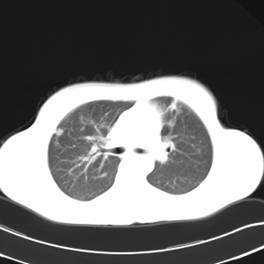

影像学资料

影像学检查:

CT左侧乳腺癌保乳治疗术后,双肺发转移瘤;

右肺中叶炎症;

X光(XXX医院的胸片——双肺转移);

MRI头颅双侧基底节区腔隙性脑梗塞、骨扫描无骨转移。

两个月后患者到医院复查CT发现,双肺发转移瘤明显实现了瘤体萎缩。